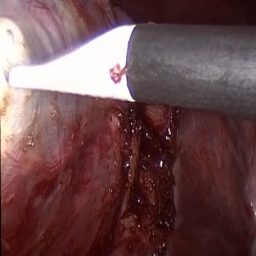

Refer to caption (a) Input Refer to caption (b) case1 Refer to caption (c) case2 Refer to caption (d) case3 Refer to caption (e) Ours Refer to caption (f) Target

Figure 4: Ablation comparisons sampled from the DesmokeData and LSD3K datasets. The first two rows are from DesmokeData and the last two rows are from LSD3K. (settings: case1 = ADA+CrossGating, case2 = DHA+CrossGating, case3 = DHA+ADA).

IV-D Ablation Studies

To validate the effectiveness and individual contributions of the core components of our proposed RGA-Net, we conducted a series of ablation experiments on the DesmokeData dataset. We systematically analyzed the impact of our key designs: the DHA module, the ADA module, and the Cross-Gating (CG) mechanism for feature fusion. In these studies, we created several variants of our network by removing or replacing one component at a time and evaluated their performance. The quantitative results of these experiments are presented in Table II, and qualitative visual comparisons are shown in Fig. 4.

IV-D1 Effectiveness of the Dual-Stream Hybrid Attention Module

The DHA module is designed to capture both local surgical details and global illumination changes by combining shifted window attention with a frequency-domain processing branch. To ablate its effect, we replaced the DHA modules in the encoder with standard Swin Transformer blocks, thus removing the spectral pathway and the hybrid attention mechanism. As demonstrated in Table II, this variant experienced a significant drop in performance. This decline highlights the importance of integrating frequency-domain information, which is crucial for handling the complex light scattering caused by surgical smoke and restoring high-frequency textural details. The results confirm that the dual-stream approach provides a richer feature representation than spatial attention alone.

IV-D2 Effectiveness of the Axis-Decomposed Attention Module

We then investigated the contribution of the ADA module, which is employed in the decoder and latent space to efficiently process multi-scale features. We created a variant where the ADA modules were substituted with a more conventional self-attention mechanism without the block and grid axis decomposition. The results in Table II show a clear degradation in performance for this variant compared to the full model. This outcome validates that factorizing attention along two distinct axes allows the model to capture both fine-grained local patterns and long-range spatial dependencies more effectively and efficiently. The ADA module’s design provides a powerful yet computationally manageable way to model complex feature relationships during the reconstruction phase.

IV-D3 Effectiveness of the Cross-Gating Mechanism

Finally, we analyzed the efficacy of the cross-gating mechanism used for multi-scale feature fusion between the encoder and decoder. We replaced our CG blocks with a standard skip-connection method, specifically simple concatenation followed by a convolutional layer, as is common in many U-Net-based architectures. As shown in Table II, this change resulted in a substantial performance decrease. This finding underscores the superiority of the bidirectional feature modulation offered by our CG mechanism. Unlike simple fusion, cross-gating allows the encoder and decoder pathways to selectively amplify relevant features and suppress irrelevant information from each other, leading to a more refined and effective integration of multi-scale context, which is vital for high-quality image reconstruction.

In conclusion, the ablation studies comprehensively demonstrate that each of our proposed components—DHA, ADA, and CG—is integral to the overall performance of RGA-Net. The full model consistently outperforms all ablated variants, proving the synergistic benefits of our architectural design for the challenging task of surgical smoke removal.